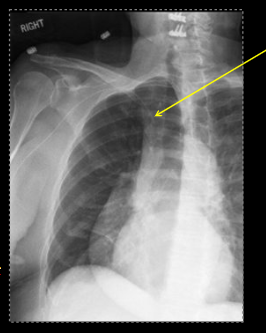

what type of tube is this?

PICC line